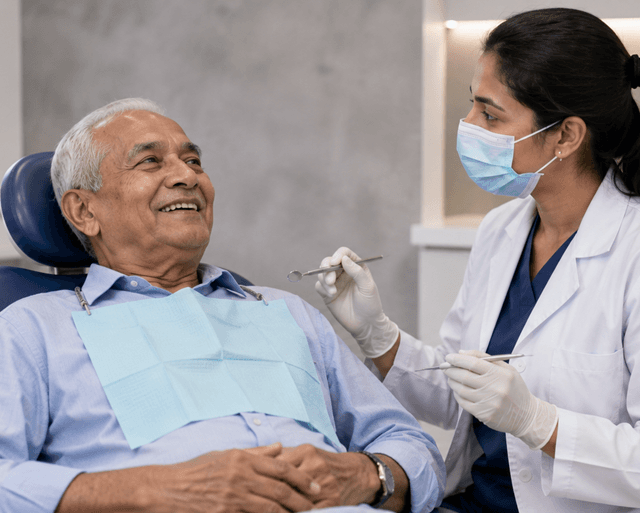

As we age, our dental needs change significantly. Seniors often experience oral health issues such as tooth loss, gum disease, dry mouth, and difficulty chewing. Proper dental care becomes essential